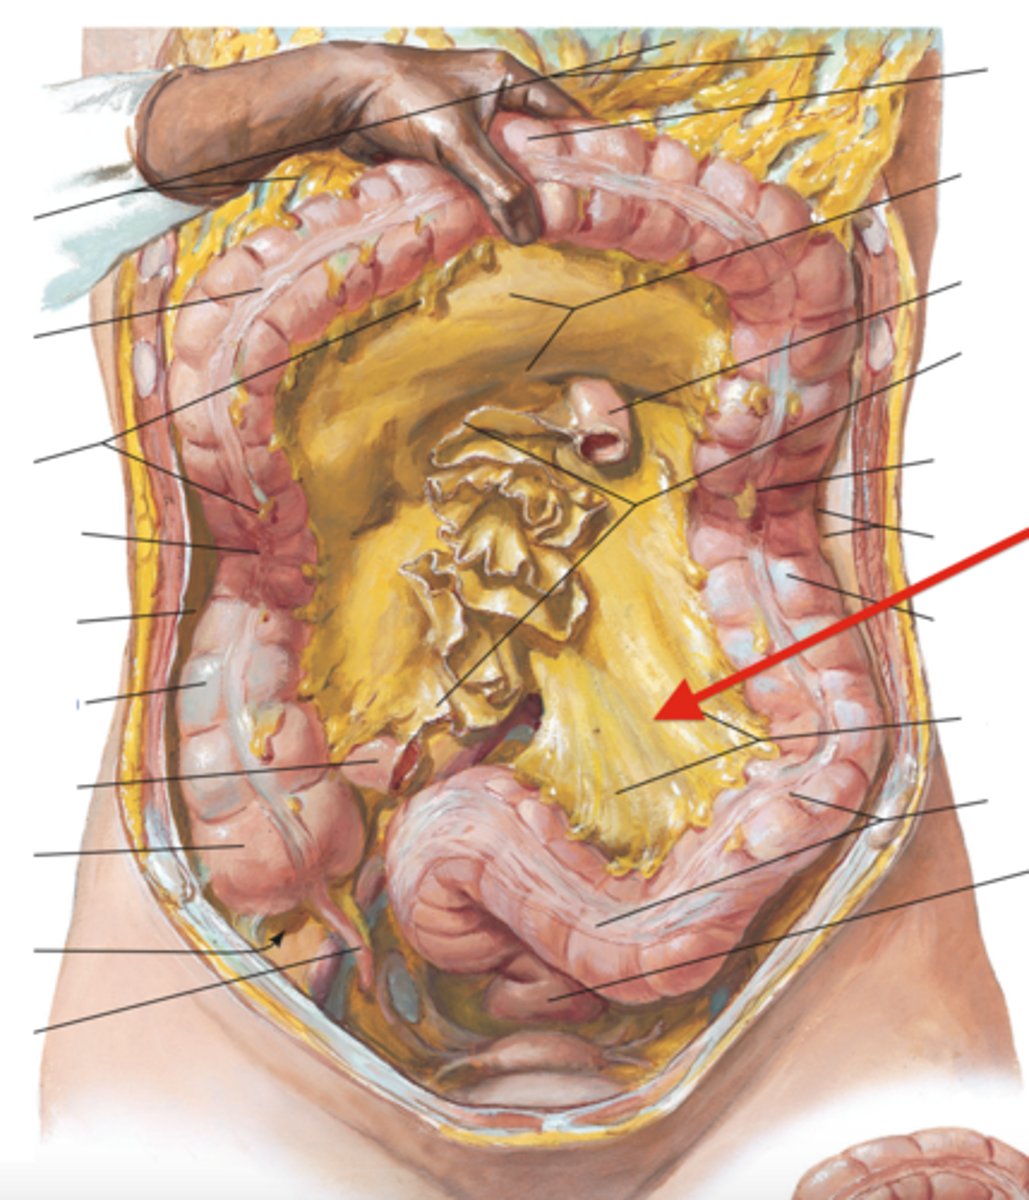

mesentery proper